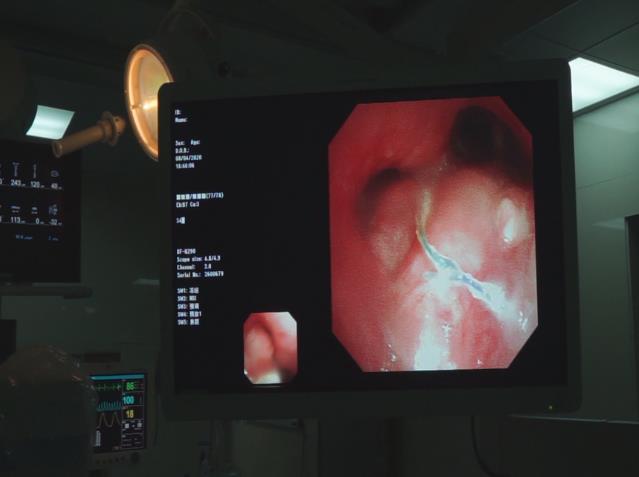

此時張先生生命危在旦夕,時間急迫,在與家屬多次溝通并取得同意后,牛院長團隊決定為他實施纖維支氣管下左側支氣管消融術+DSA引導下左側支氣管支架置入術。

2020年4月8日,牛院長團隊通過DSA+CT技術不僅快速準確找到狹窄的支氣管,還更為清楚地看到腫瘤及其他周圍組織的關系。在氣管鏡下,牛院長熟練進行著進導絲、送置入器、釋放支架等等步驟;隨后在微波射頻消融設備下,將穿刺針刺入縱膈上的腫瘤部位,利用射頻發熱原理使腫瘤部位壞死。歷時一個半小時手術順利結束。